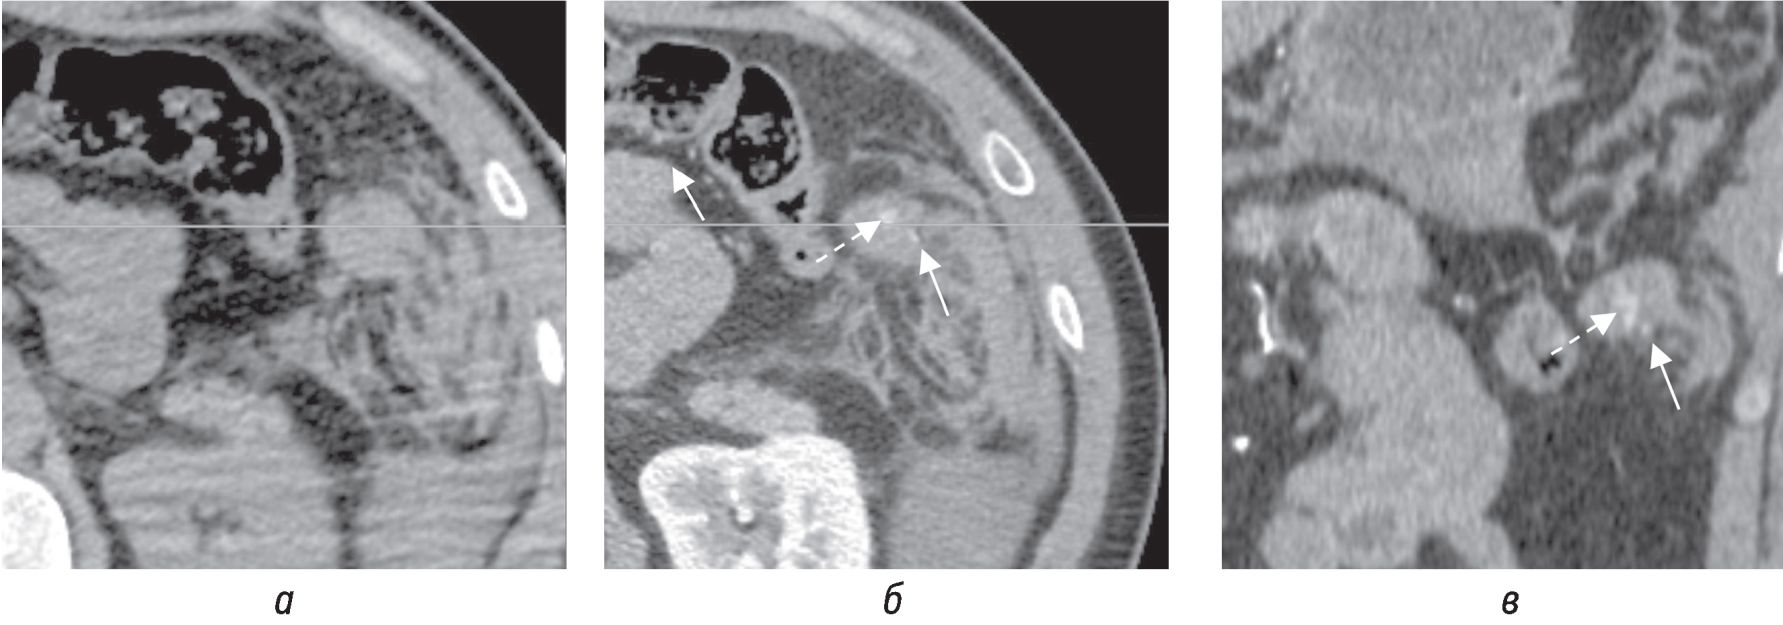

При КТ с внутривенным контрастированием экстравазация контрастного вещества была выявлена в 8 случаях из 10, а во время оперативного вмешательства только у 4 из 8 было выявлено активное кровотечение. В одном случае [11] не было ни экстравазации при КТ, ни активного кровотечения при операции. В одном случае [5] на КТ экстравазация не визуализировалась, при оперативном вмешательстве выявлено активное кровотечение. В нашем случае только при ретроспективной оценке КТ-изображений была выявлена экстравазация контрастного вещества из сальниковой артерии (рис. 4, 5), а при операции выявлена напряженная гематома пряди большого сальника.

Рис. 4. КТ-изображения в аксиальной плоскости в нативную (а) и артериальную фазу (б) и соответствующее изображение в артериальную фазу во фронтальной плоскости на уровне экстравазации (б, в; пунктирная стрелка) из сальниковой артерии (б, в; сплошная стрелка)